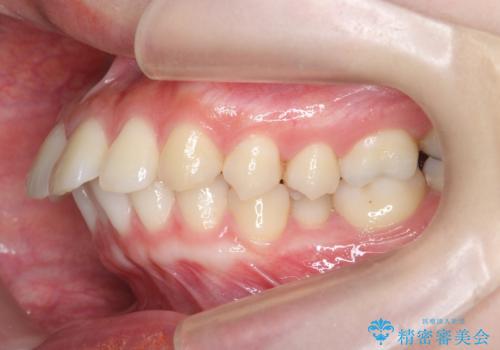

カリエール・マイクロインプラントを併用した歯の突出を改善する大きな遠心移動

- 口が閉じづらく、突出し歯が出っ歯に見えてしまうことの改善を求めて来院されました。

通常このような場合、抜歯してのワイヤー矯正治療も選択肢に入りますが、患者様の強い希望により抜歯を行わずマウスピースによる治療を選択しました。

カリエール・マイクロインプラントを用い、時間はかかりましたが大きく歯の後方移動が達成され、前歯の見た目が大きく改善されました。